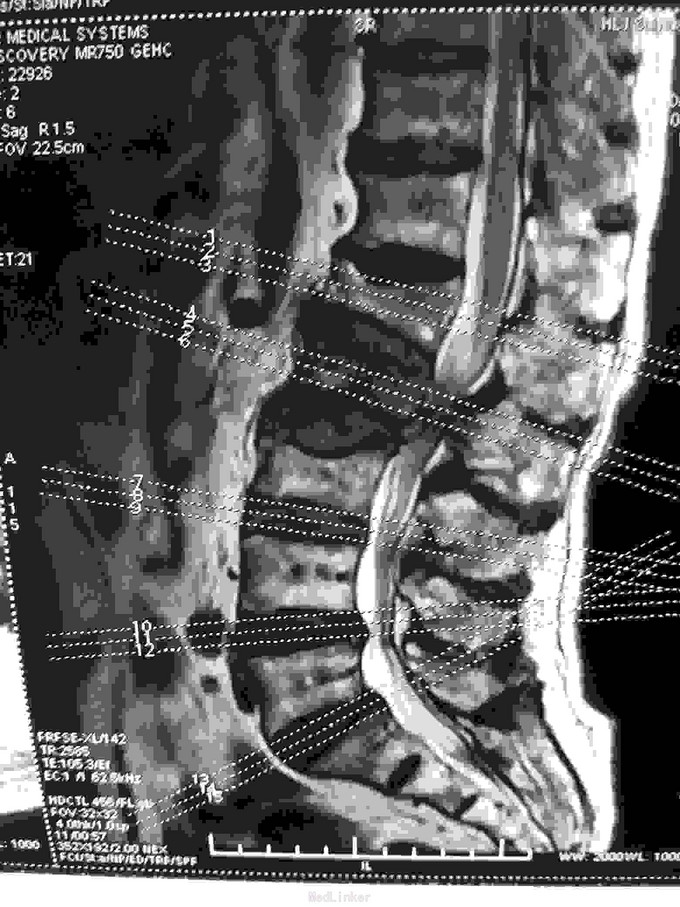

根据病史查体诊断:腰间盘突出症待确诊。应用消肿营养神经镇痛治疗。一天。查核磁共振示:腰椎多节段间盘突出伴椎管狭窄。第二腰椎骨破坏侵及椎板。部分突入椎管,脊髓受压。诊断:腰间盘突出伴椎管狭窄。第二腰椎转移癌,脊髓受压。经与家属沟通,查双肺CT:双肺下叶炎症。肺部纤维化。可见肿瘤阴影。肋骨及胸膜受累。胸椎部分骨破坏。最终诊断:双肺癌,胸椎,腰椎骨转移,脊髓受压。多节段腰椎间盘突出。病人至肿瘤科治疗。